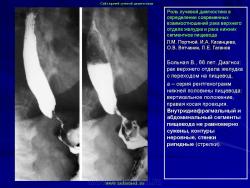

Мои пять копеек.

А.В. Шумаков.

То, что здесь инфильтрация стенок, я уверен до дрожи в коленках...

Говорите что язва желудка, да он весь - как ригидная трубка,

Перистальтики нет и в помине, и больная живет как на мине...

А с рельефом вообще тут не сладко, хоть есть в антруме плоская складка...

Не спасем... иль зовите мессию, очень трудно здесь брать биопсию...

Ну а в теле желудка сужение, циркулярное и без движения....

Так что в нашей работе не брак, мы не зря заподозрили рак...

Что же делать - кого не спроси, нам наверно ответят УЗИ!!!